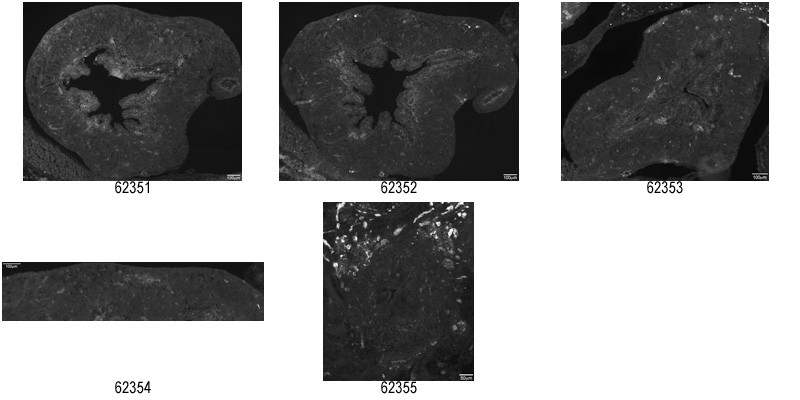

GUDMAP:22753:

embryonic day 18.5; Trpv1tm2Bbm/Trpv1tm2Bbm

Note: This specimen was generated and annotated by the lab of Janet R. Keast, University of Melbourne. Images are shown in a rostral to caudal direction.

GUDMAP:22914:

GUDMAP:22915:

Note: This specimen was generated and annotated by the lab of Janet R. Keast, University of Melbourne.